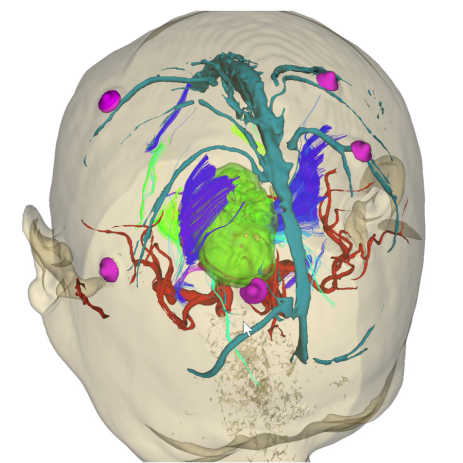

面對如此復雜的病情,孫國柱教授團隊決定綜合應用AR技術、皮層及皮層下電刺激技術、電生理監(jiān)測技術、細胞級熒光引導技術來為手術保駕護航。其中,EndoSCell?細胞級熒光導引技術成為了手術中的關鍵角色,這臺全球唯一的術中實時在體細胞級顯影設備,能夠幫助醫(yī)生術中直接裸眼看到高清、實時、動態(tài)的細胞圖像,從細胞層面區(qū)分腫瘤組織與正常組織,從而實現細胞級精準切除,最大范圍切除腫瘤的同時最大程度保護功能。

手術室內,氣氛緊張而專注。孫國柱教授團隊已于術前應用3D-slicer軟件進行多模態(tài)影像融合建模,并于術中應用AR技術投射到手術區(qū)域以定位腫瘤,做到胸有成竹。

結合3D建模及AR技術定位腫瘤